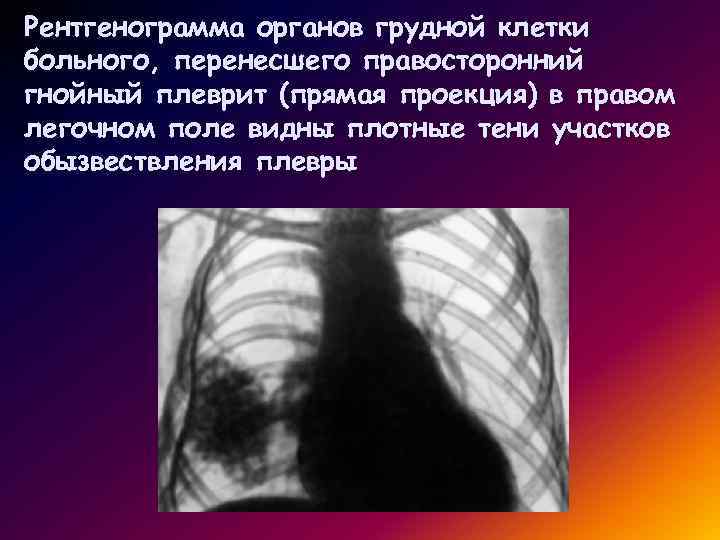

Ячеистая деформация легочного рисунка: медицинская визуализация